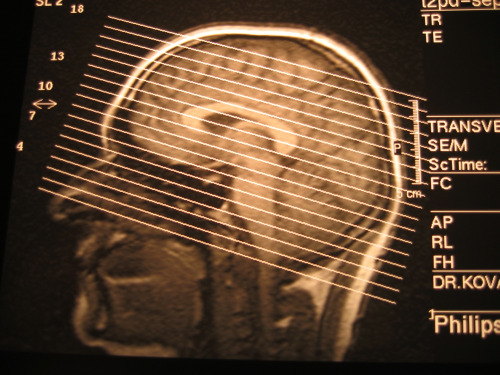

Tutto questo si realizza grazie all’amigdala, una struttura cerebrale a forma di mandorla che risiede nel lobo temporale davanti all’ippocampo.

Le sue funzioni principali sono quelle di immagazzinare le notizie e di comandare una reazione in particolari situazioni, con pensieri ed azioni che richiamano alla memoria esperienze dello stesso tipo e che hanno insegnato al cervello a reagire.

Queste emozioni che scaturiscono da questo nucleo di neuroni sono indipendenti dalla nostra volontà e quindi dal pensiero razionale.

Tutto questo si realizza grazie all’amigdala, una struttura cerebrale a forma di mandorla che risiede nel lobo temporale davanti all’ippocampo.

Le sue funzioni principali sono quelle di immagazzinare le notizie e di comandare una reazione in particolari situazioni, con pensieri ed azioni che richiamano alla memoria esperienze dello stesso tipo e che hanno insegnato al cervello a reagire.

Queste emozioni che scaturiscono da questo nucleo di neuroni sono indipendenti dalla nostra volontà e quindi dal pensiero razionale.